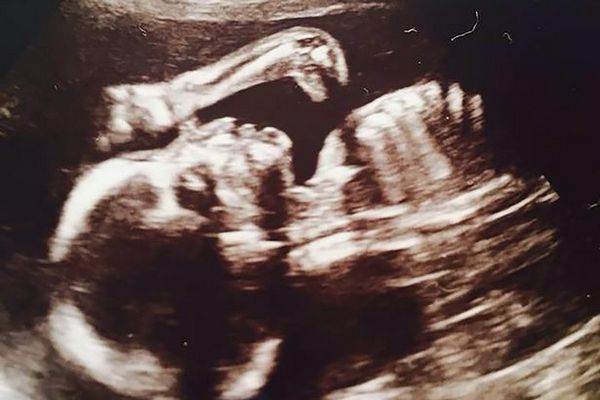

Сделавшая УЗИ беременная жительница Ливерпуля, 29-летняя Линн Салливан, обомлела, получив сюрприз из Юрского периода. Кроме малыша, она увидела на снимке шею и голову маленького динозавра.

Врачи в больнице, которые делали УЗИ, не обратили на длинную шею ящера никакого внимания. Первым заметил странное явление приятель Линн, Джеймс Флетчер. Он указал будущей матери на пятно, которое больше всего походило на крохотного бронтозавра - ископаемого ящера из Юрского периода.

Изумленная Линн Салливан поделилась загадочным снимком в Интернете. Она сообщила, что за пару недель до обследования ходила в кино на фильм «Парк Юрского периода», премьера которого состоялась в начале июня.

На момент ультразвукового исследования ребенку было около 20 недель. Известно, что это девочка, которую родители хотят назвать Рути-Лу.